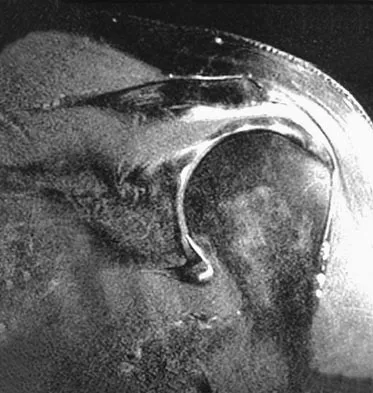

Figure 20 shows the MRI scan of a 20-year-old athlete who has a painful shoulder. This pathology is most commonly seen in

Explanation